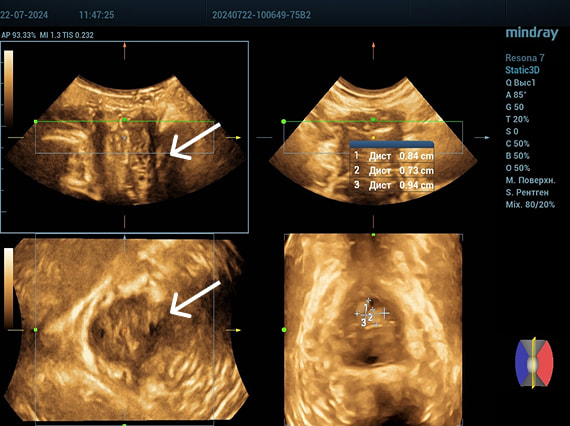

УЗИ тазового дна для уточнения

расположения филлера 2

Эхограммы периуретральной области

Трансперинеальный доступ, конвексный датчик.

Слева от уретры округлое образование с четкой капсулой и мелкодисперсной взвесью размерами 1,5×1,0 см (филлер с воспалением), справа — анэхогенное овоидное образование (филлер).

Эхограмма 3